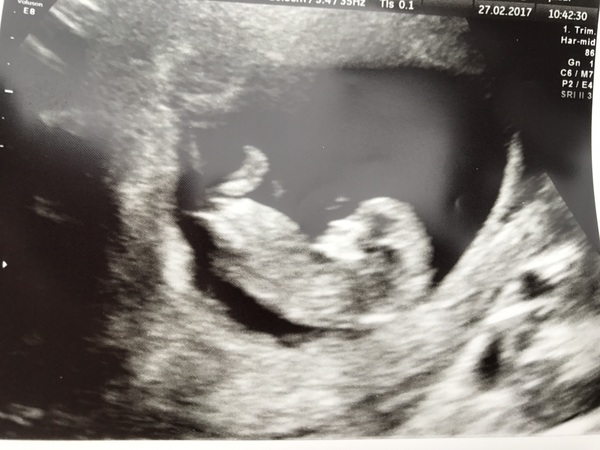

Had my 12 week scan today, due date changed by one day from 9th to 10th September. NT measurement was 1.5mm which I'm happy with, though we're going to wait for the full results of the screening before telling anyone. We've decided against a big announcement too, we're still a bit wary, much more relaxed and excited now than we have been, but don't want to make a big deal. So just going to tell people as and when we see them. We won't be hiding it - I'm my sisters bridesmaid in August, so won't be able to hide it then, that's for sure!